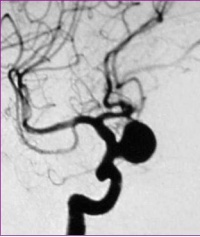

3.脑血管造影是确诊颅内动脉瘤必须的检查方法,对判明动脉瘤的准确位置、形态、内径、数目、血管痉挛和确定手术方案都十分重要。DSA更为清晰。,经股动脉插管全脑血管造影,可避免遗漏多发动脉瘤。病情在三级以下,脑血管造影应及早进行,三级和三级以上病人可待病情稳定后,再行造影检查。及早造影明确诊断,尽快手术夹闭动脉瘤,可以防止动脉瘤再次破裂出血。首次造影阴性,可能因脑血管痉挛而动脉瘤未显影,高度怀疑动脉瘤者,应在3个月后重复造影。

(1)以出血为首发征像时,临床怀疑动脉瘤而行血管成像(DSA、CTA、MRA)可证实动脉瘤的存在,一般无需鉴别,但应注意假阳性和假阴性的存在。假阳性如颈内动脉起始部、后交通动脉起始部漏斗样增粗如正常现象,血管转折处在MRA上易误为异常,两段狭窄间正常管腔易误为动脉瘤等。假阴性如动脉瘤破裂或痉挛导致造影时不能显示等。这方面CTA较DSA和MRA有明显优势,它可以对单枝血管进行曲面重建并旋转观察,有利于分析动脉壁的结构是否正常,有利于发现无造影剂充盈的瘤体等。